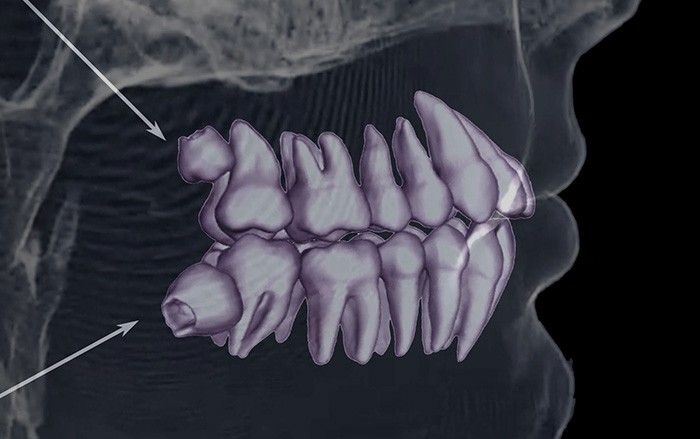

사랑니는 우리 입속에 가장 뒤에 난 어금니를 말하며, 전문용어로 설명해 드리면 제3대구치라고 하며 얼굴을 중심으로 좌우로 8번째 자리하고 있는 치아를 말합니다. 사랑니는 사춘기 이후에 자란다고 합니다. 사춘기에는 여러 가지 감정을 느끼게 되고 그 감정 중 하나가 사랑이라는 감정이지요. 그래서 이 치아를 사랑니라고 부른다고 합니다.